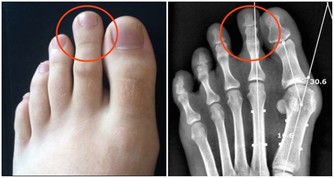

上述的兩類疾病是牙齦炎發展的兩個階段,都是牙齦受病毒感染所致,大多患者會出現口臭、牙齦腫痛的症狀,而且在刷牙時通常會引起牙齦出血。

如果出現牙齦出血而一直拖延不去治療,病情惡化到一定程度時,還會損害到患者的顎骨,造成牙齒脫落。可見該疾病不止會對口腔造成嚴重損傷,還會危害到患者的其他部位。